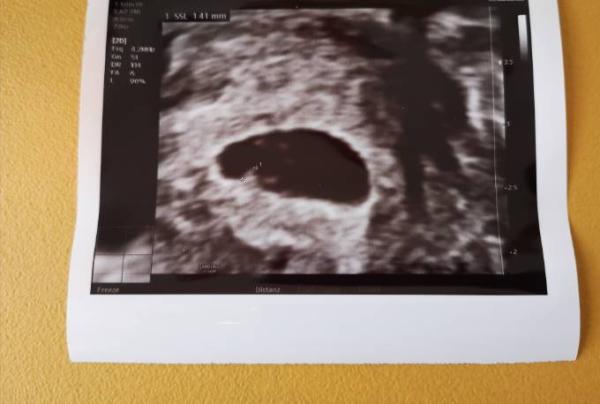

Ich hatte heute den ersten FA Termin. Das Herzchen schlägt Ich bin bei 6+1 aber der Arzt meinte er würde den ET um 5 Tage zurückdatieren. Er schaut aber am 09.09 nochmal. Ich bin erstmal happy Unser kleiner Eckhocker hat mir die Tränen in die Augen getrieben

Bild zu Herzschlag ❤️ - Forum für April - Mamis